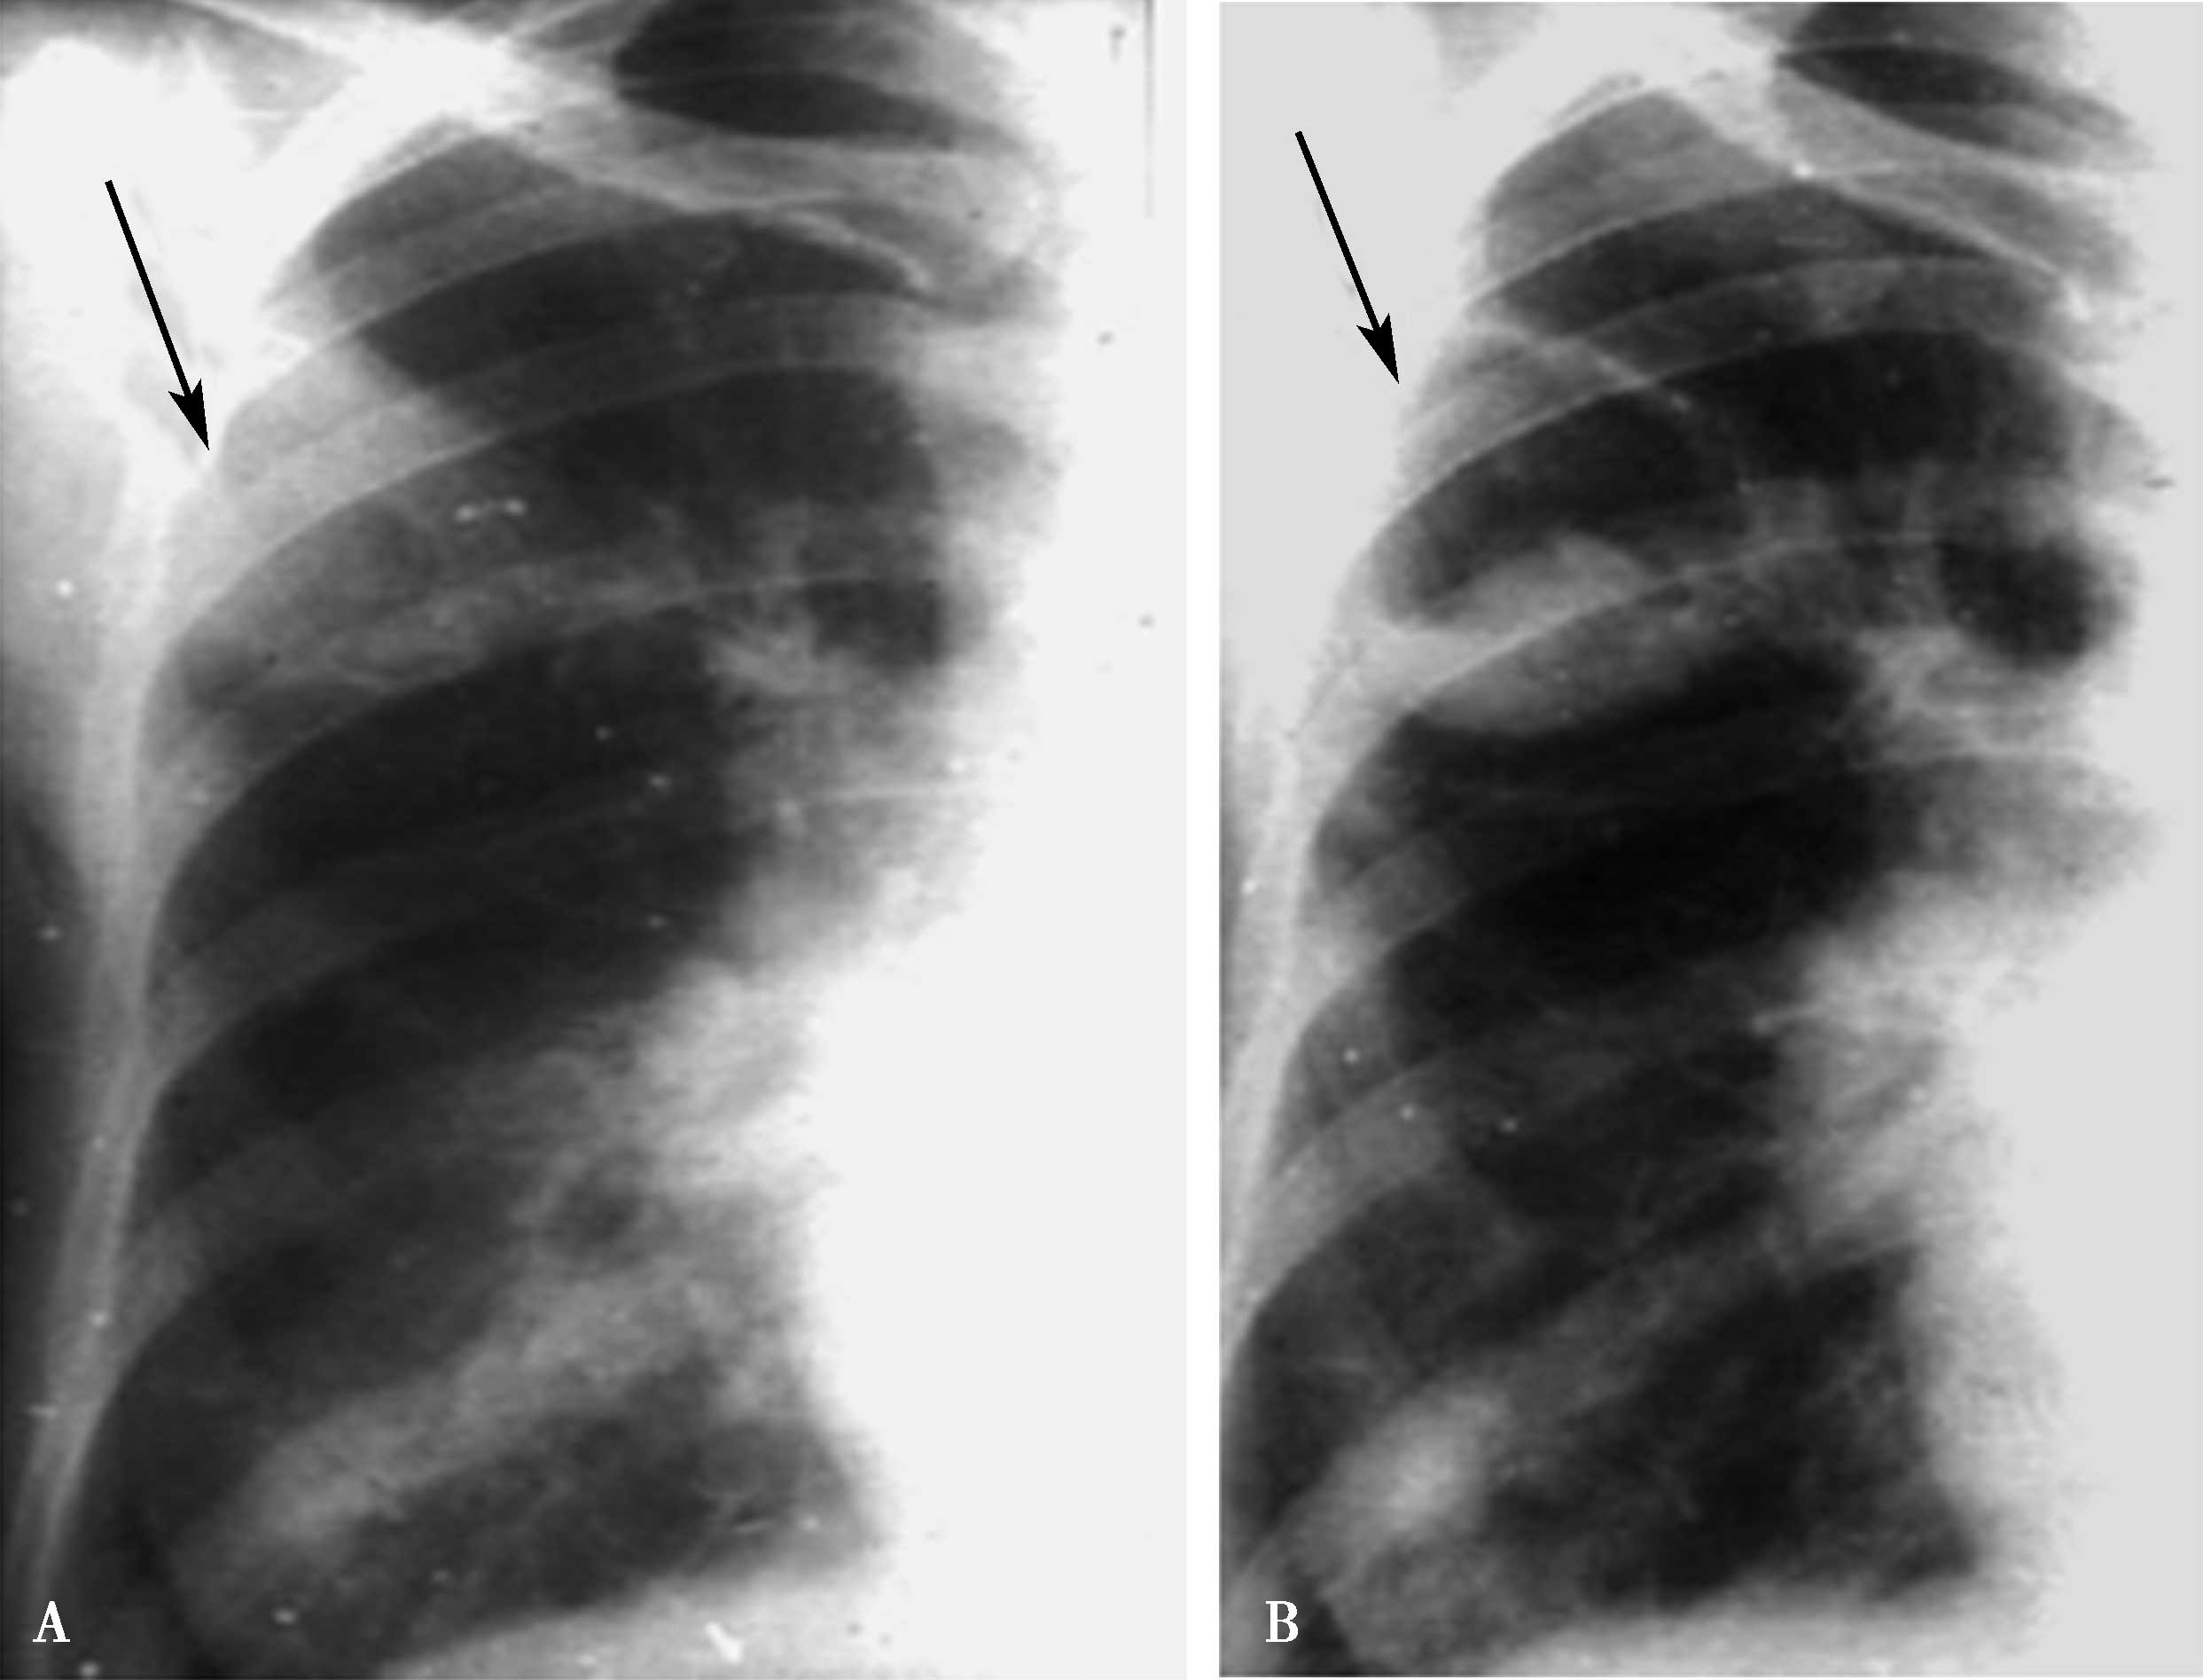

(一)左心房增大(图7-1-2)

1.远达片

左心房耳部膨隆;气管隆突角度开大;左心房高度增大时,可以向心右缘凸出(图7-1-2A↑)。

2.左前斜位

心脏后上缘膨隆,左主支气管抬高(图7-1-2B↑)。

3.右前斜位

心后缘膨隆,服钡食管中段压迹,左心房增大推压食管向后移位(图7-1-2C)。

4.左侧位

心后缘膨隆,服钡食管中段压迹,依左心房增大程度推压食管向后移位。

图7-1-2 左心房增大征象

A.远达片;B.左前斜位;C.右前斜位